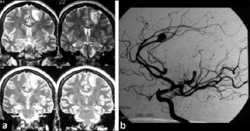

Ante la sospecha de enfermedad cerebrovascular, se necesita identificar la lesión y su ubicación y obtener información sobre el estado estructural del parénquima del cerebro y su condición hemodinámica como consecuencia de la lesión. La evaluación neuropsicológica de sujetos con daño producido por enfermedad cerebrovascular está enfocada en conocer las funciones afectadas y depende del tipo de evento. En el infarto cerebral se estudia por imágenes radiológicas los aspectos topográficos de la lesión, especialmente antes de las 24 horas del inicio del trastorno súbito. Los más utilizados son la tomografía computarizada, la resonancia magnética y el estudio del flujo sanguíneo regional cerebral.